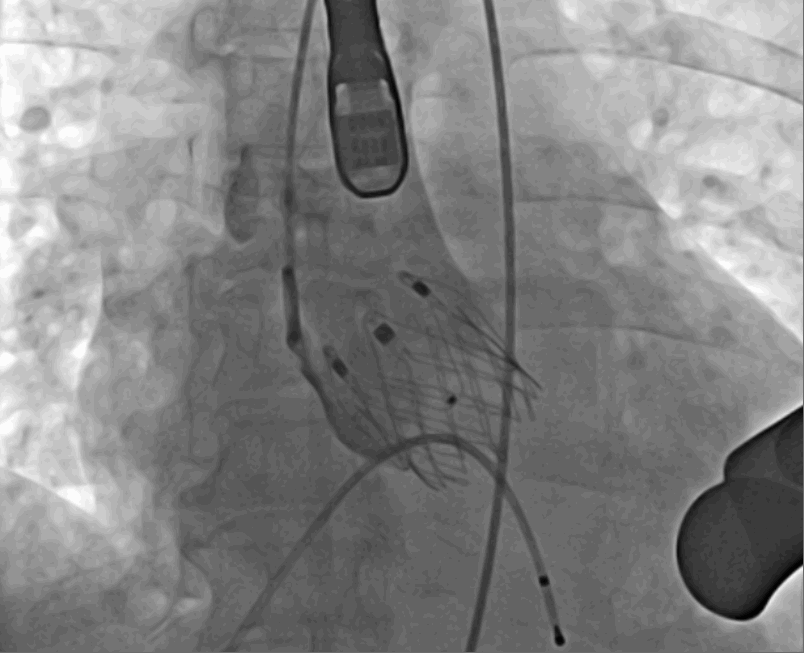

术后DSA影像

手术采用经心尖入路,对患者进行全麻后,在左侧心尖处做3-4cm微创手术切口,在DSA及超声引导下手术顺利完成。从导入器械到完成瓣膜置入,仅耗时约10分钟。术后即刻主动脉瓣反流程度由术前大量反流转为消失,患者于导管室拔除气管插管,次日由ICU转入普通病房。